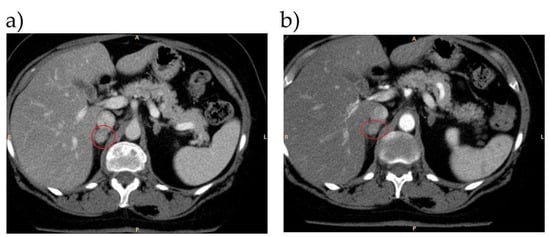

5.2. Case 2

Are These AVS Results Interpretable?

| 2 | SIT and CCT: both positive | Left adrenal adenoma | AVS not interpretable for inadequate catheterization. Use of unconventional indices (MAI and MI) with demonstration of left aldosterone lateralization | Left adrenalectomy | Normotension and normal potassium levels at last follow-up (3 months) |